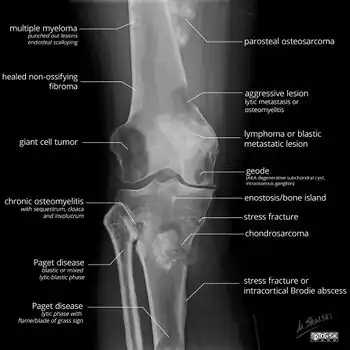

A bone tumor may be felt on examination, following which a plain X-ray is usually carried out.[4][13] Imaging is interpreted with the location of the lesion and the person's age being taken into account.[14]

X-ray appearances of different types of bone tumors in > 30 years.